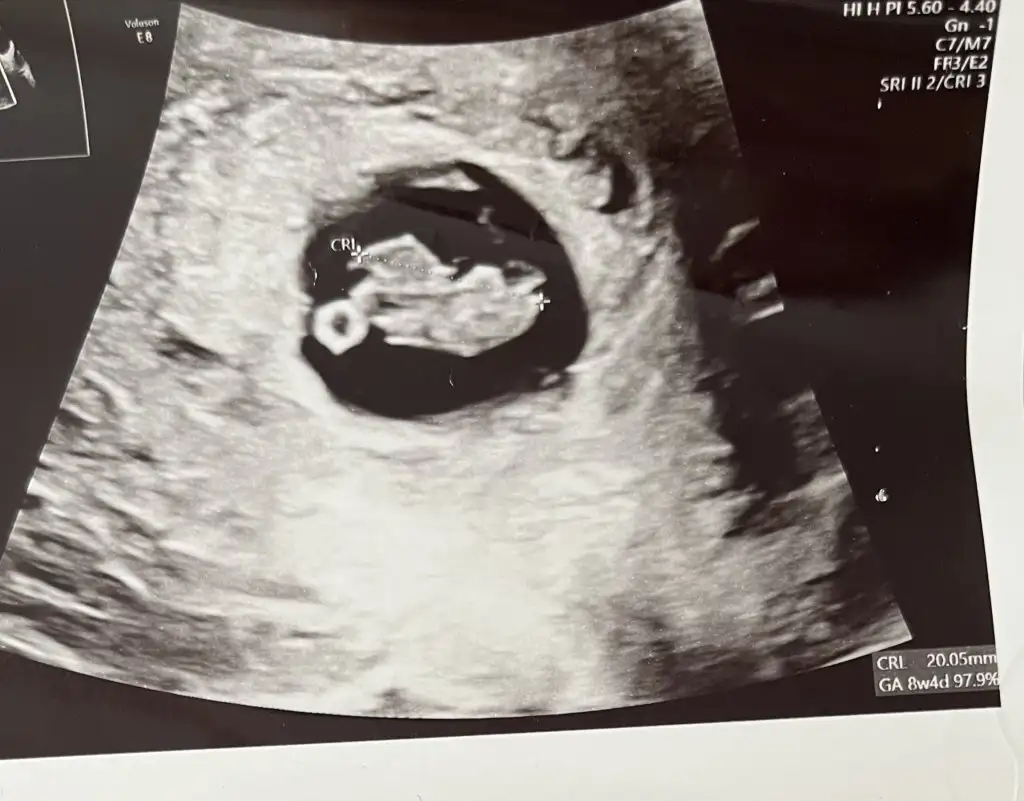

Bana da yorum yapar mısınız çok merak ediyorum D DantewnRica etsem bana da bakar mısınız? Bu resimde 10+1.Kalp atımı 8. Haftada 150 civarıydı en son gittiğimde sormadım şimdiden teşekkürlerEki Görüntüle 3419037

Canım muhtemelen kızBana da bakar mısınız? 8+5